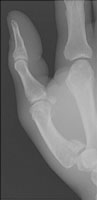

The Bennett fracture is an intraarticular fracture of the base of the first metacarpal. The fracture must involve the first carpometacarpal joint to be called a Bennett fracture. The action of the abductor pollicis longus causes distraction of the fracture fragments. The volar base of the first metacarpal stays with the trapezium.

- Click on the image for a larger versionBPA radiograph of the first digit. This view better defines the Bennett fracture.